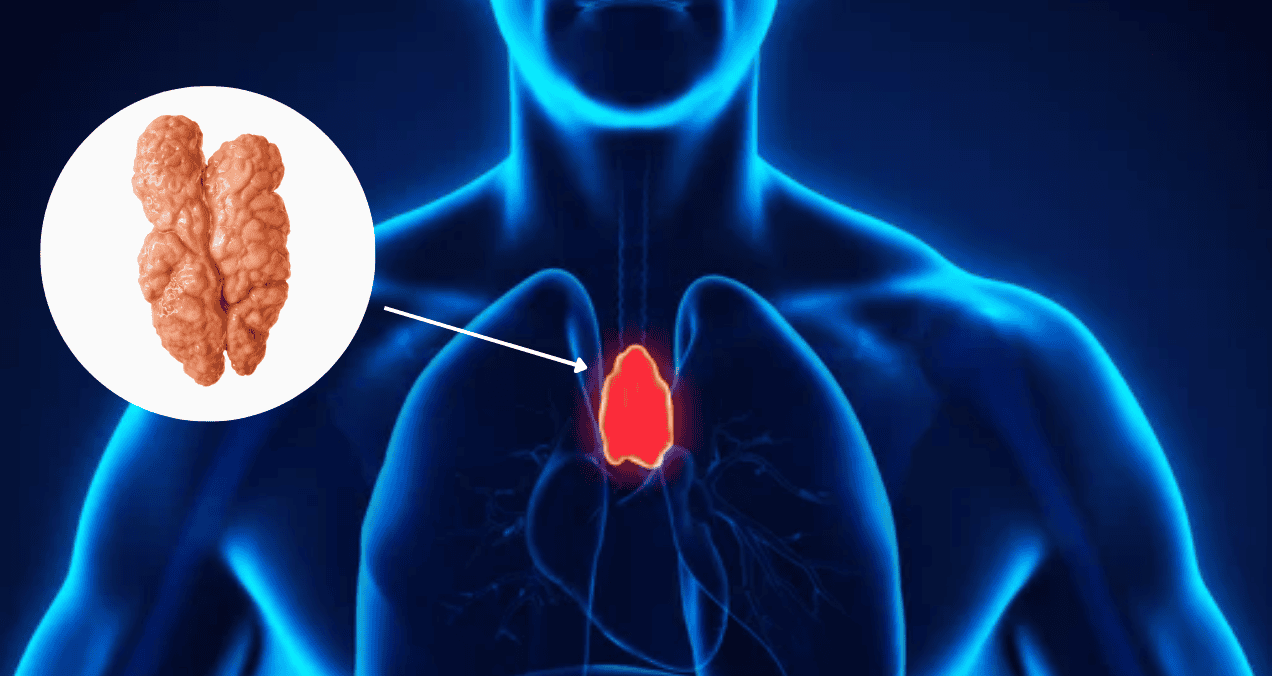

Hasta hoy día, se tenía el conocimiento de que un factor clave para superar algunas adicciones/trastornos mentales, se encuentra en la vía de recompensa más antigua y conocida: el sistema dopaminérgico mesolímbico, compuesto por neuronas que se proyectan desde el área tegmental ventral hasta el núcleo accumbens, una estructura clave en la mediación del procesamiento emocional y de la motivación.

Los investigadores descubrieron que aproximadamente el 30% de las células del área tegmental ventral -que es parte del cerebro medio- son neuronas GABA.

Mediante ejemplares de ratones machos y hembras, los científicos demostraron que las neuronas GABA de largo alcance que van desde el área tegmental ventral hasta el núcleo accumben ventral, pero no dorsal, participan en el comportamiento de recompensa y refuerzo.

Demostraron que esta proyección Gabaérgica inhibe a las interneuronas colinérgicas, que son clave en el aprendizaje relacionado con la recompensa.